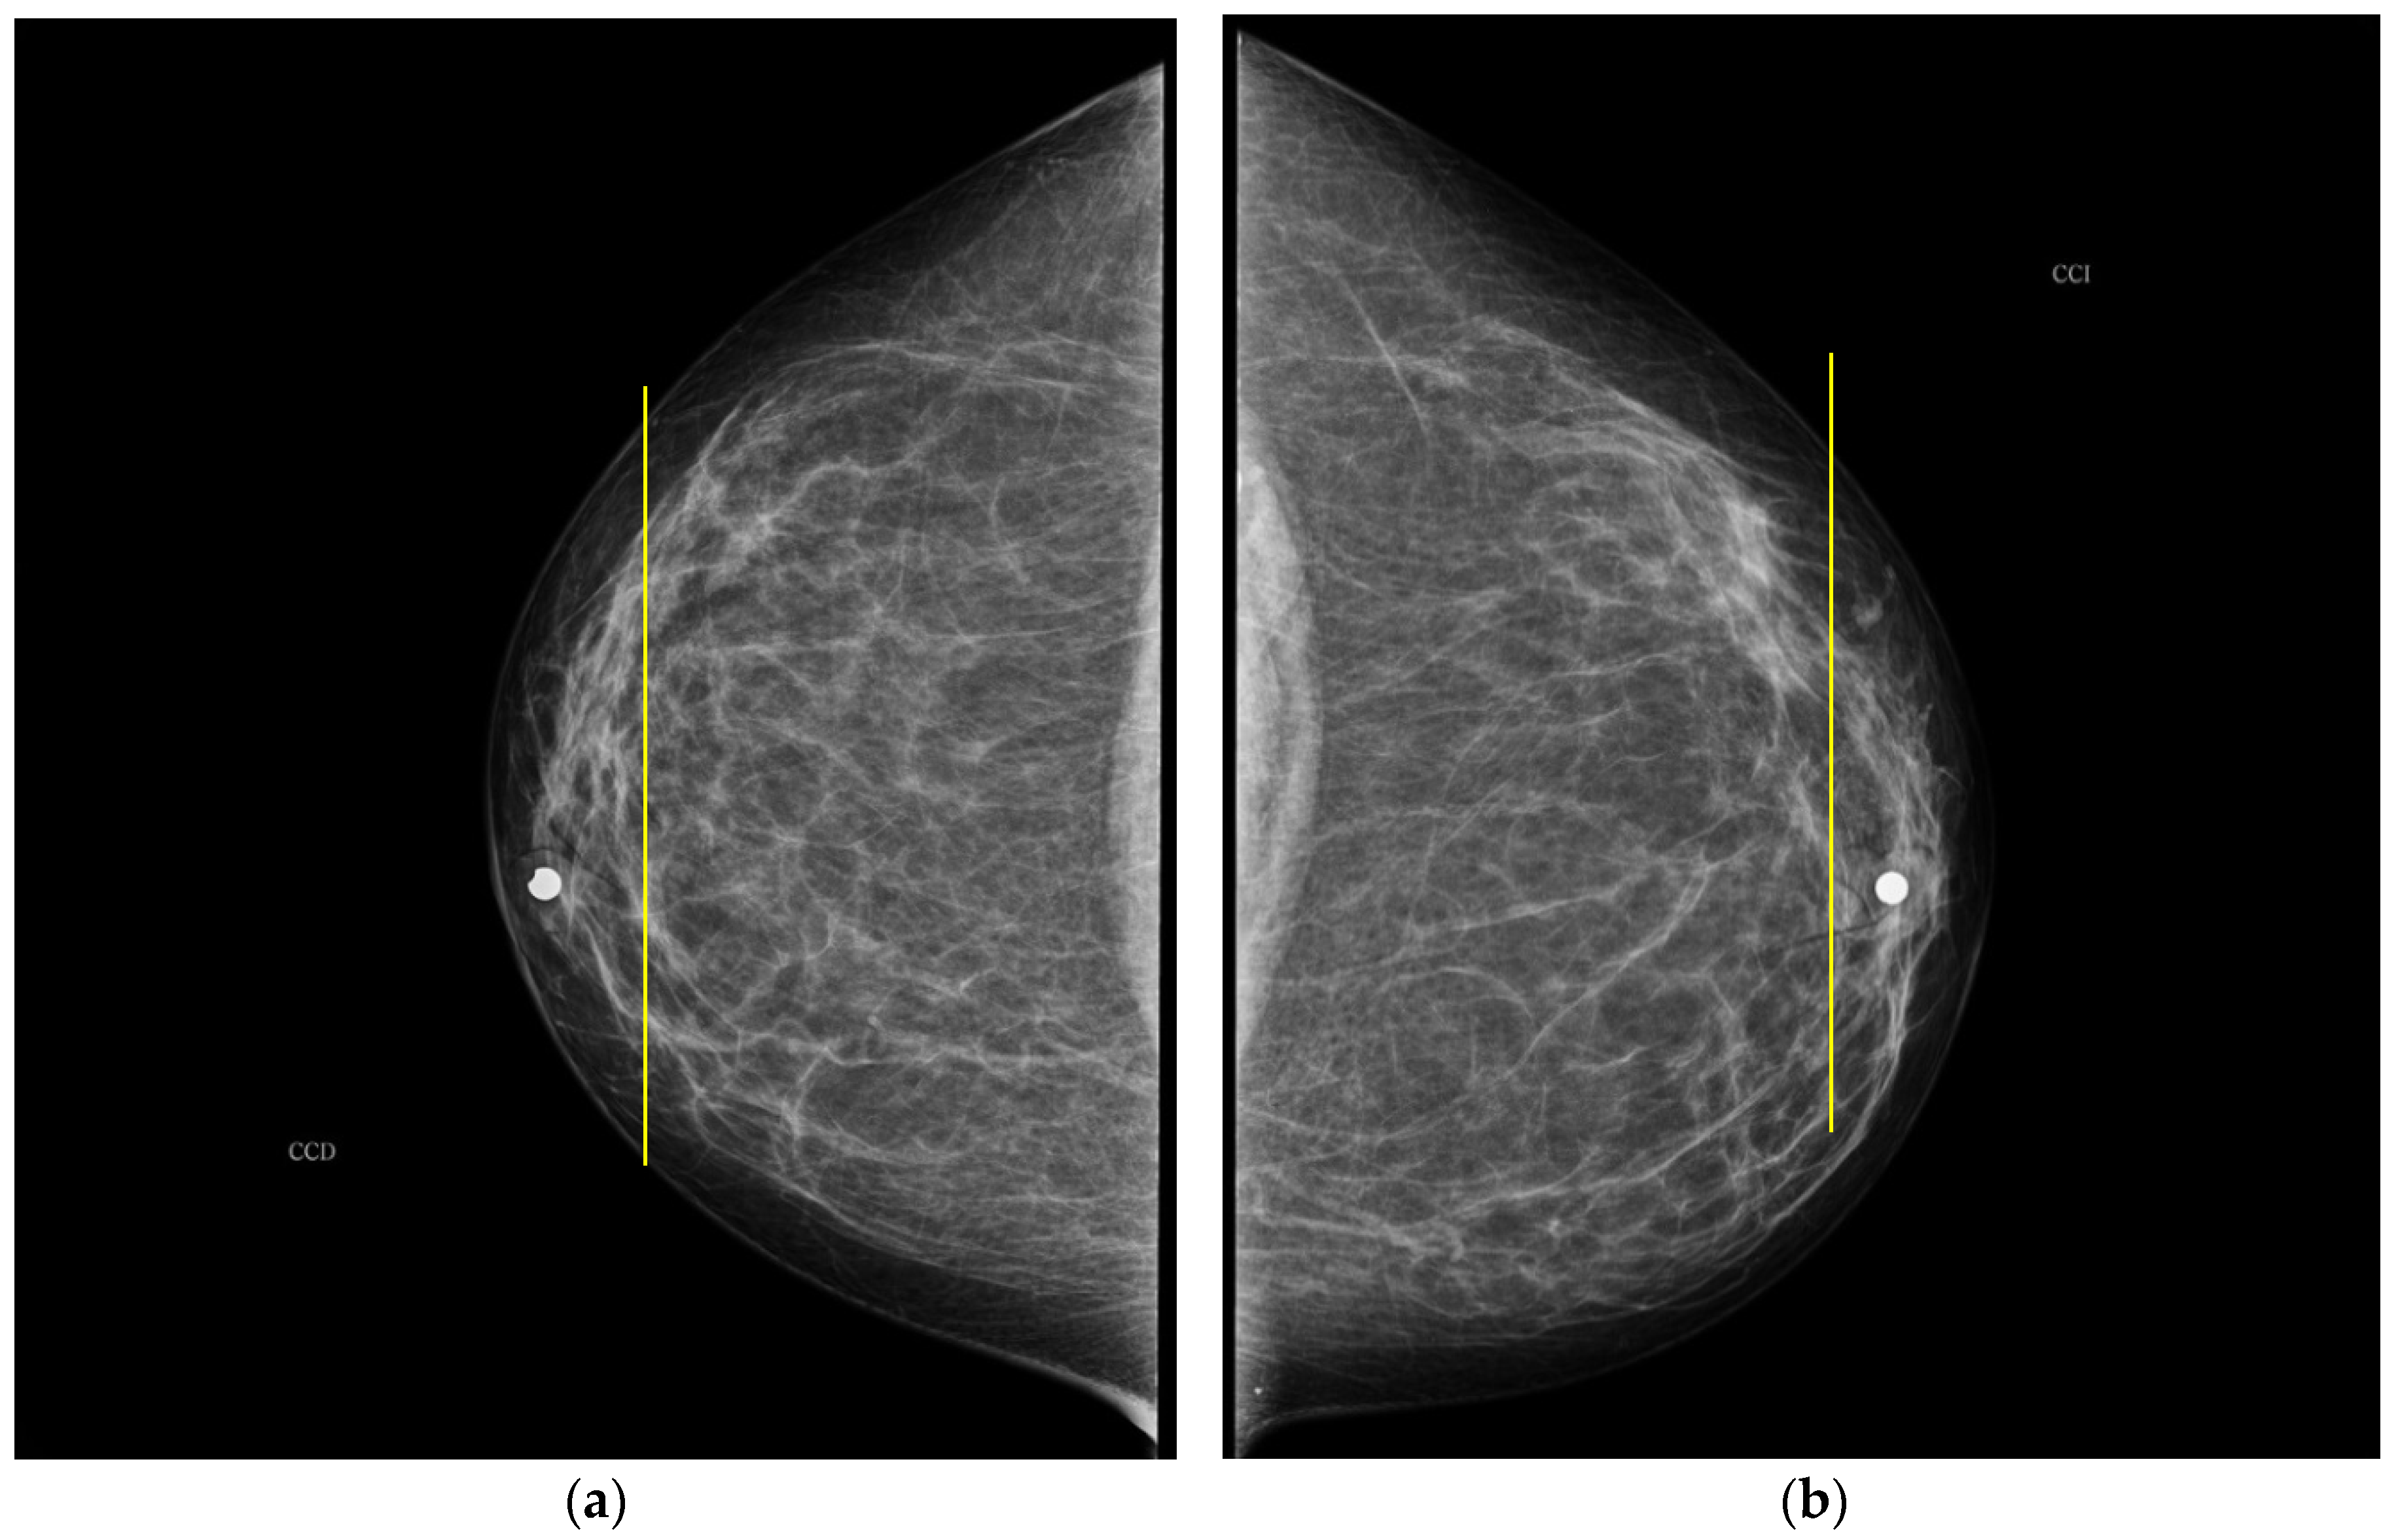

The PBD evaluated by the specialist for participant 1 is BI-RADS c for both breasts, and the outcome for the described clustering method is BI-RADS d and c for right and left breast, respectively. The CC mammography images for both breasts are presented in Figure 7, where the respective electrode ring positions are illustrated by the vertical yellow line. As it can be observed, there is a greater breast tissue in the plane covering the vertical yellow line of right breast than that corresponding to the left one. That is the reason why the resulting sectional PBD of right breast is greater than the left breast.

Figure 7. CC mammogram images of participant 1 and relative electrode ring position (yellow vertical line): (a) right breast; (b) left breast.